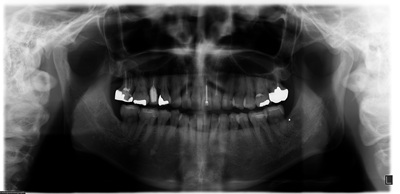

術前パノラマ![]() |

52歳の女性の患者様です。長年にわたり定期的にメインテナンスを続けておられ、歯ぎしりの自覚があり、ナイトガードを早い段階から使用されていました。右上の奥で噛むと違和感があるとのことで来院され、前から5本目と7本目の歯の根に亀裂が見つかりました。どちらも過去に治療を重ねてきた歯でしたが、内部まで亀裂が進行しており、残念ながら保存は難しい状態でした。

奥の7本目の歯は骨の高さが足りず、上あごの空洞(上顎洞)に非常に近い位置にありました。一方で、その手前の5本目の歯は骨の厚みは十分でしたが、噛む力が強く、歯ぎしりの影響を受けやすい位置でした。同じ上あごの奥歯でも条件がまったく異なっていたため、それぞれに適したインプラントを選択しました。